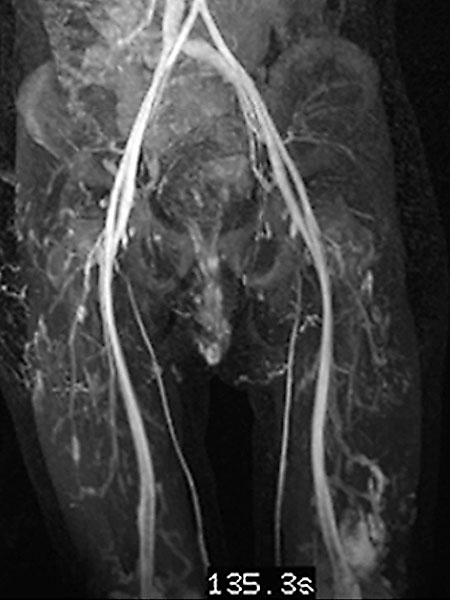

In der Spätphase der dynamischen, zeitlich hochaufgelösten, kontrastmittelunterstützten MR-Angiographie 135 Sekunden nach i. v. Kontrastmittelapplikation kommt es zu einem langsamen, verzögerten Kontrastmittelpooling in der Läsion. Eine arteriovenöse Malformation mit ihrem schnellen Durchfluss kann somit klar ausgeschlossen werden. Ebenfalls langsame Anreicherung der zweiten Läsion am lateralen distalen linken Oberschenkel.